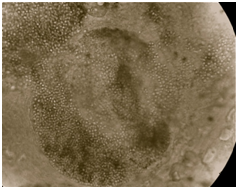

Out of a total 152 samples, 138 (90.79%) scrapings were KOH positive and 140 (92.11%) culture positive. All 100 patients were culture positive. Out of 140 culture positive samples, 138 (98.57%) were T. interdigitale (Figure 9), 1 (0.71%) Trichophyton violaceum (T. violaceum) and 1 (0.71%) T. rubrum. Out of 100 patients 98 had single or multiple site infection due to T. interdigitale, one male child (1%) had tinea capitis due to T. violaceum and one male adult (1%) had tinea corporis due to T. rubrum. None of the patients had dual infection due to two different dermatophyte species. At least one anatomic site was positive in patients with the involvement of the multiple sites (Figure 10).

Figure 9 LPCB mount of T. interdigitale with spiral hyphae, microconidia in grape like clusters and club shaped macroconidia.